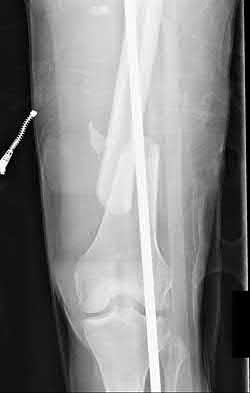

1. # A 32-year-old male sustains the injury shown in Figure A and undergoes treatment as shown in Figure B. Following placement of this implant, what is the best technique to confirm it is not too proud proximally?

The safe zone for tibial nail placement as seen on radiographs is just medial to the lateral tibial spine on the anteroposterior radiograph and immediately adjacent and anterior to the articular surface as visualized on the lateral radiograph.

Tornetta et al specifically located the safe zone for nail entry in a study using fresh frozen cadaver knees. The authors found that the safe zone for nail placement is located 9.1+/-5 millimeters lateral to the midline of the plateau and three millimeters lateral to the center of the tibial tubercle. The width of the safe zone averaged 22.9 millimeters and was as narrow as 12.6 millimeters.

The starting point of the of the nail can be best viewed on the lateral knee radiograph, an example of which is shown in Illustration A. Illustration B shows the "sweet spot" for nail insertion as defined by Tornetta.